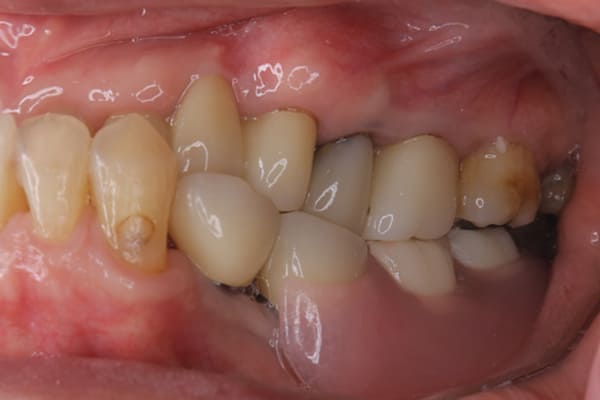

上下互い違いで咬む歯同士がない状態のため、柔らかいものを舌で潰され召し上がっておられました。

かみ合わせがなく、すれ違い咬合と言われる難症例に分類される状態でした。

上の歯は重度歯周炎でぐらぐらで、お痛みも繰り返しており、抜歯が必要な状態でした。

検査の結果、下の3本のうち、2本は何とか根は残せる状態であったため、虫歯の治療、根の治療を行い残すことに努めました。

上下の歯同士のかみ合わせがない状態で長年過ごされていましたので、当初はどこで咬んだら良いかわからない状態でしたが、治療用入れ歯を用い、調整を行い、本来のかみ合わせに戻すことが可能になりました。

初めての入れ歯が総入れ歯の場合は、大きな違和感を感じられる方が多いですが、上顎に金属を用いた入れ歯にすることで、厚みを薄くし違和感を抑え、お食事での温熱も感じられるようになりました。

下の総入れ歯は外れやすいため大きな虫歯はありましたが、虫歯治療を行い、根のみ残せた2本の歯に磁石を利用することで歌われた際も外れない入れ歯の設計としました。

下顎は舌があるため、上顎と比較すると総入れ歯の場合、外れやすい傾向があります。患者様はまだお若く、お肉がお好きだったとのこと、またお歌もご趣味とのことで、ご相談の上、なるべく外れない設計としました。

磁石を用いた入れ歯の設計により上下の入れ歯は、お食事やお歌を歌われ大きなお口を開けても外れない状態が可能になりました。

当初、ハンバーガーを召し上がりたいと仰っていましたが、今ではステーキも召し上がられ、カラオケでも入れ歯は外れず、滑舌が全く変わったと喜んで下さりました。